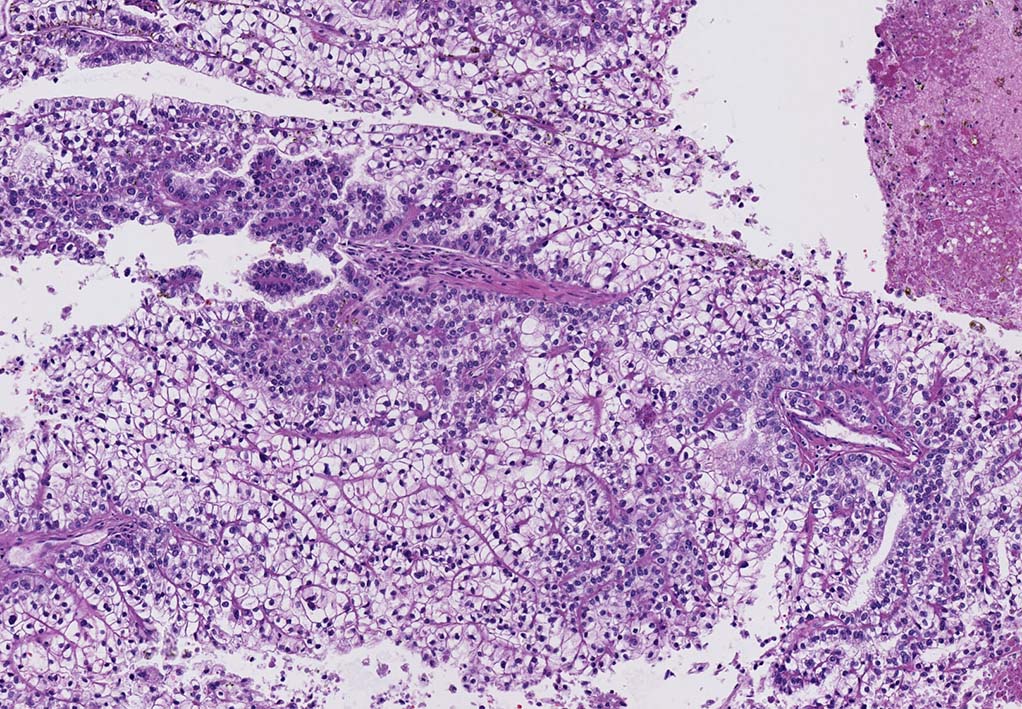

mark-g.gif Clear cell renal cell carcinoma(ccRCC) 淡明細胞型腎細胞癌

腎細胞癌の約70%を占める(65-70% in adult RCC)淡明または好酸性の細胞質を有する細胞と壁の薄い,繊細で鹿角状(staghorn-shaped)の豊富な血管網から構成される悪性腫瘍. 形態は多彩.

carbonic anhydrase IX(CA9)および CD10が陽性. CK7, AMACR(P504)は陰性.

典型例では,VHL遺伝子(3p25-26)の不活化, del(3p),, 低酸素誘導因子hypoxia induced factor(HIF)の発現上昇を伴う特徴的な分子背景を有する.;形態は多彩であるが, 特徴的な分子基盤をもつ腫瘍である.